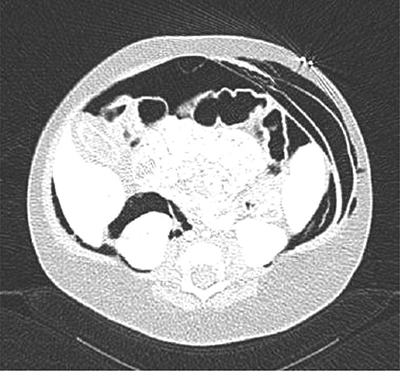

A whole body low-dose computed tomography (CT) scanner showed a tension pneumothorax leading to decreased cardiac output. It also showed extensive deep tissue emphysema (latero-thoracic and right-cranial), pneumomediastinum, pneumopericardium, and important retroperitoneal free air without pneumoperitoneum (Figures 4 and 5).

Figure 4

Whole body low-dose CT scanner.

Latero-thoracic and right-cranial subcutaneous emphysema along with massive free air (e.g., pneumomediastinum and pneumopericardium).

Figure 5

Latero-thoracic and right-cranial subcutaneous emphysema along with massive free air.

Further, it showed abdominopelvic ascites, periportal, and perivascular edema. There was cleavage of all abdominal layers produced by the free air (Figure 6).

Figure 6

Cleavage of all abdominal layers produced by the free air.